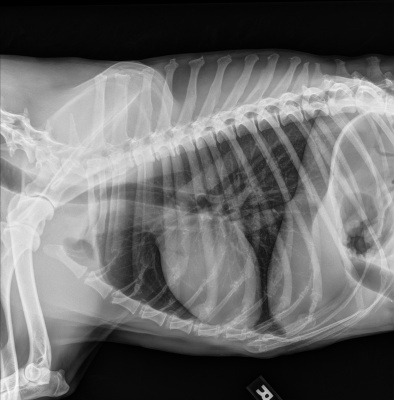

At Urgent Vet, abdominal radiographs showed a small intestinal obstruction caused by two mineralized foreign objects. At IVS, thoracic radiographs were taken to rule out metastatic neoplasia. IDEXX’s consult report indicated no intrathoracic evidence of metastatic disease.